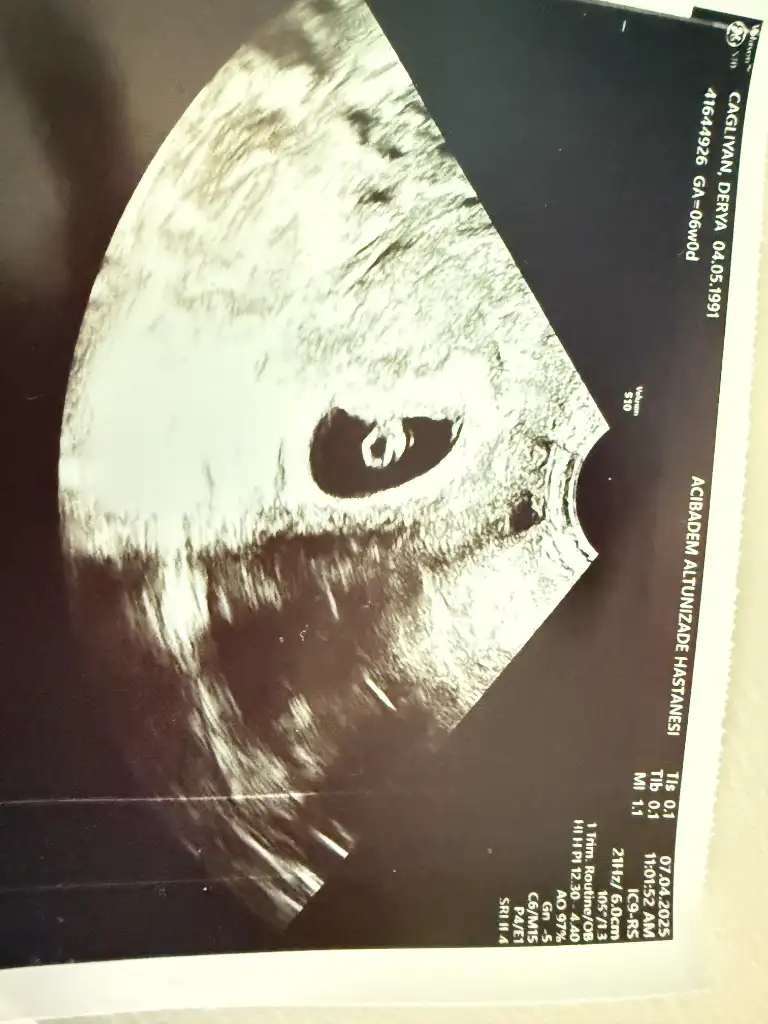

Attığınız ultrasonda yolksac denen o kese hiç görünmüyor ama o yüzden plasenta da belli olmuyor yorum yapamayacağımbana da bakabilir misiniz? 6+3 haftalık abdominal

Yazmayı unuttum vajinalKızlar 6-8 haftalık ultrason görüntülerinizi atın tahmin yapalım . Ya da cinsiyeti öğrenen annelerimiz 6-8 haftalık görüntülerini atsın bize de fikir olsun

Kız olabilir diye düşünüyorumİlk defa böyle bişey yapıyorumhenüz çok erken 6+1 burada, inşallah sağlıkla devam eder ama konuyu görünce de dayanamadım yorumunuzu beklerim

Abdominal görüntüyse eğer kız olabilirBenimkide 6 buçuk haftalık görüntü çok belli değil sanki ama yorumlayabilen varsa beklerim